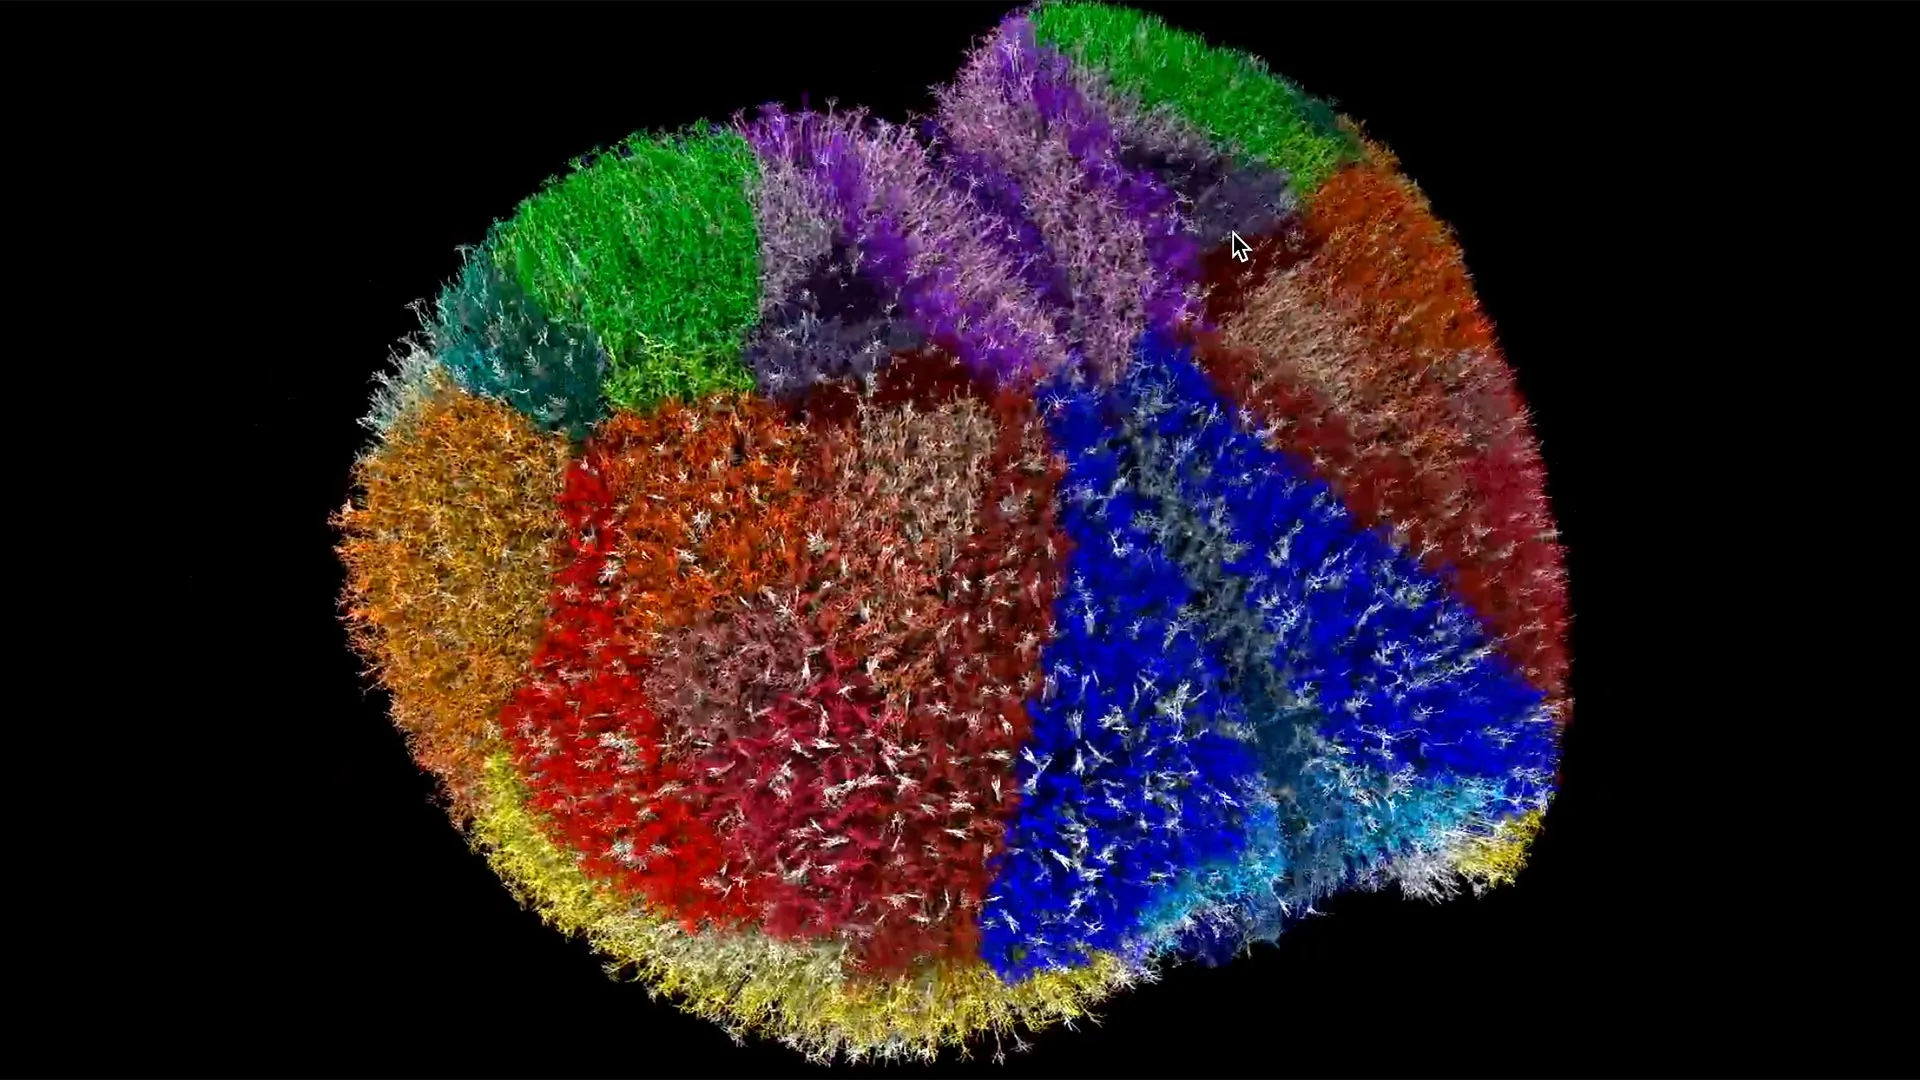

باستخدام قوة أحد أسرع أجهزة الكمبيوتر العملاقة على هذا الكوكب، أنشأ العلماء واحدة من أكثر عمليات محاكاة دماغ الحيوان شمولاً وواقعية من الناحية البيولوجية على الإطلاق. إن عملية إعادة البناء الرقمية هذه لقشرة الفأر بأكملها تمنح الباحثين طريقة جديدة لاستكشاف وظائف المخ من خلال إعادة إنشاء حالات مثل مرض الزهايمر أو الصرع داخل بيئة افتراضية. فهو يسمح لهم بتتبع كيفية انتقال الضرر عبر الدوائر العصبية والتحقيق في العمليات المرتبطة بالإدراك والوعي. تتضمن المحاكاة ما يقرب من عشرة ملايين خلية عصبية، و26 مليار مشبك عصبي، و86 منطقة دماغية متصلة، مما يلتقط البنية والنشاط بدقة عالية.

يجمع هذا الجهد التعاوني بين المعرفة العميقة بعلم الأعصاب وقوة المعالجة التي تتمتع بها آلة عالمية المستوى. ساهم معهد ألين في الأساس البيولوجي للدماغ الافتراضي باستخدام بيانات من قاعدة بيانات أنواع خلايا ألين وأطلس اتصال ألين، بينما تولى فوجاكو العمليات الحسابية الضخمة اللازمة لإنشاء النموذج.

وباستخدام مجموعة أدوات نمذجة الدماغ التابعة لمعهد ألين، قام الفريق بتحويل البيانات البيولوجية إلى عملية إعادة بناء رقمية فعالة للقشرة الدماغية. لمحاكاة السلوك العصبي الحي، قامت أداة تدعى نيوليت (Neulite) بتحويل المعادلات الرياضية إلى خلايا عصبية افتراضية قادرة على النبض، والإشارات، والتواصل كما تفعل الخلايا العصبية الحقيقية.

إن مشاهدة المحاكاة يشبه مراقبة نشاط الدماغ الحي. يستنسخ النموذج تفاصيل دقيقة عن بنية الخلايا العصبية، ونشاط المشبك العصبي، والإشارات الكهربائية عبر أغشية الخلايا. وقال يامازاكي: “إنه إنجاز تقني، ولكنه مجرد خطوة أولى”. “الله موجود في التفاصيل، لذلك أعتقد أنه في النماذج التفصيلية الفيزيائية الحيوية.”